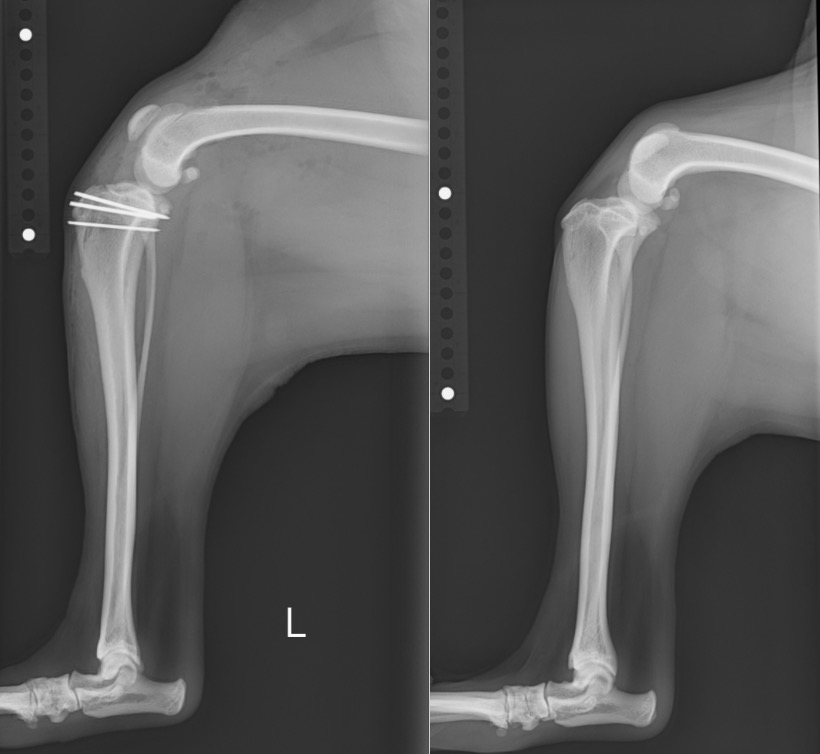

術前・術後のX線を見比べると、膝蓋骨が真ん中に整復されていることが分かります。

白く見えるのはステンレス製のピンであり、脛骨粗面転移という手技を行ったために使っています。

右後肢 【左:術後 / 右:術前】